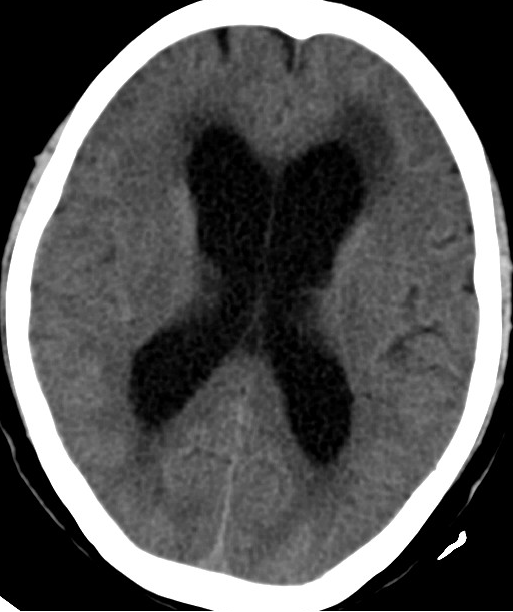

2014-2-10 CT

仍诉头痛,调压150——170

2014-3-17 CT

头痛无明显好转,调压170——190

2014-10-17 CT

仍时有前额部疼痛,程度轻,调压190—200